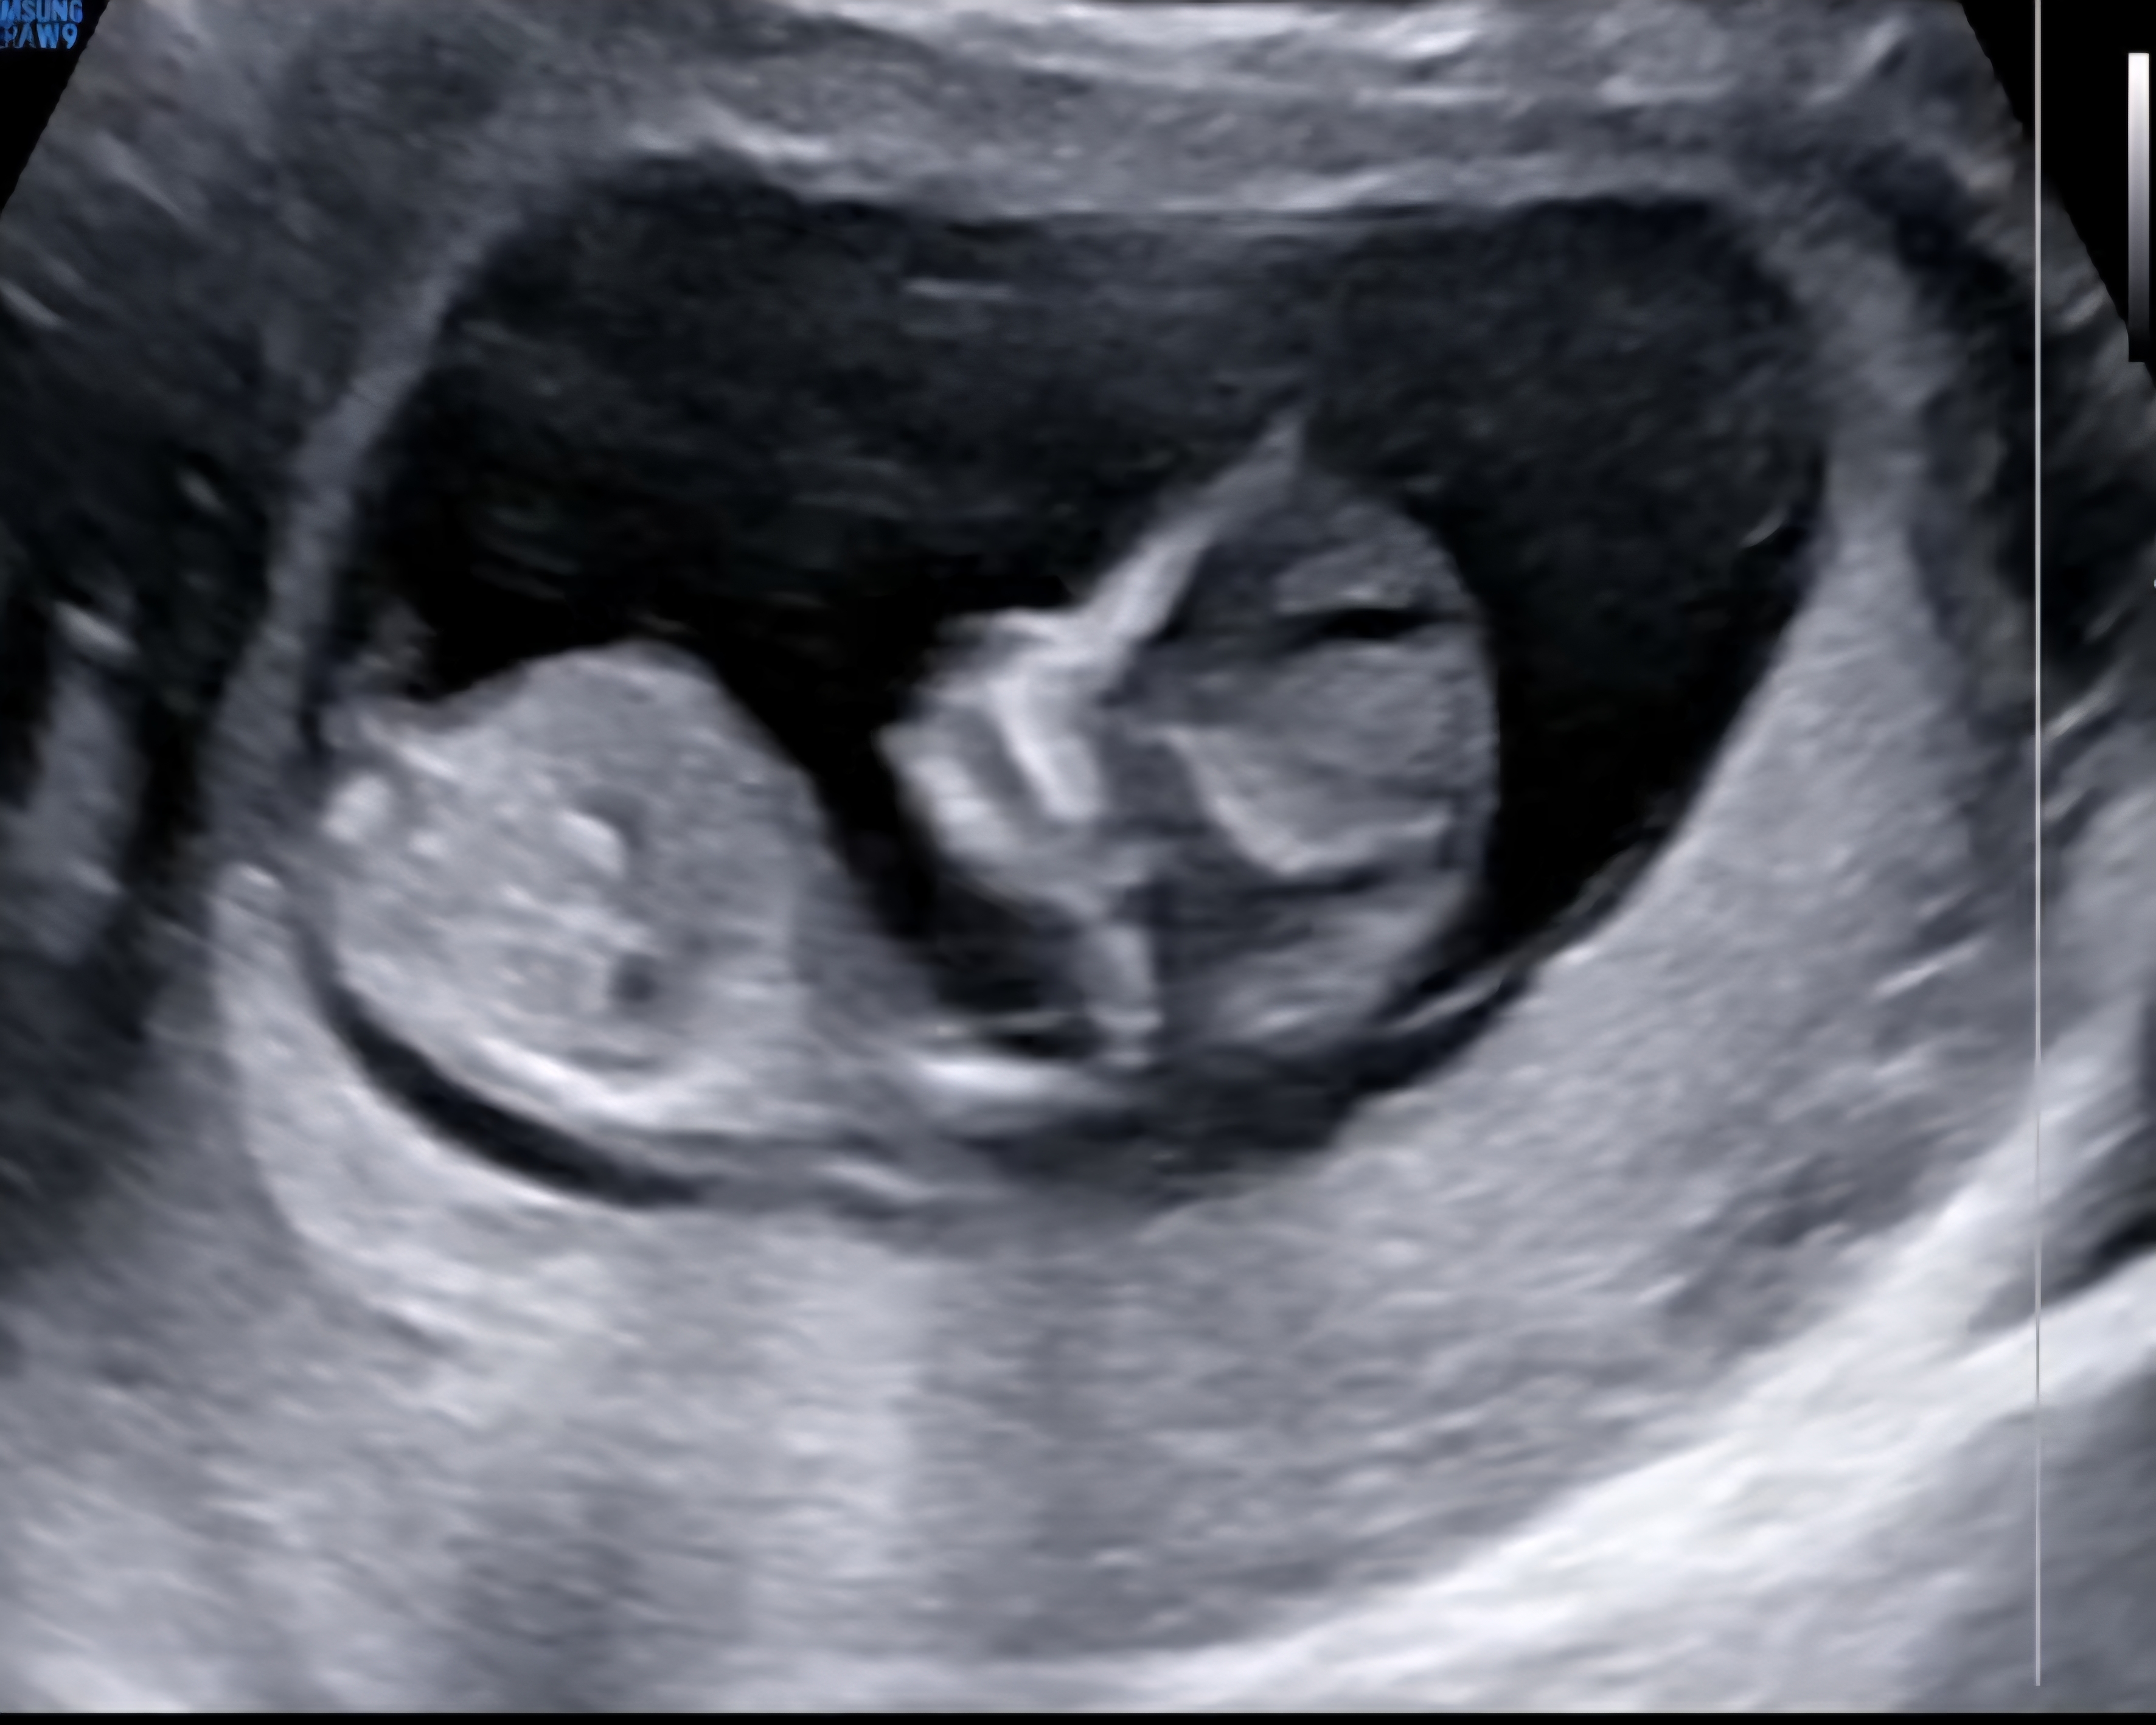

12주차 초음파 성별 벌써 궁금해요♡♡

12주차 엄마예요^-^ 12주밖에 안된 초음파 사진인데 코가 벌써부터 오똑한게 남자로 태어나도, 여자로 태어나도 기대가 되네요 두근두근♡♡ 저희 아가는 남자아이일까요?? 여자아이일까요??